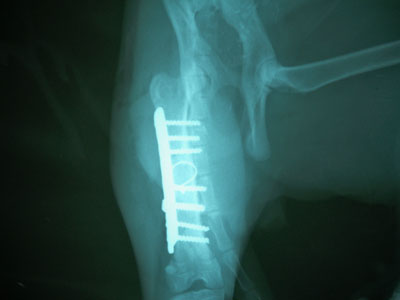

Γάτος ηλικίας 7 μηνών με κάταγμα μεσότητας διάφυσης μηριαίου οστού .Πραγματοποιήθηκε ορθοπεδικό χειρουργείο με μεταλική πλάκα κοχλίες και ορθοπεδικό σύρμα. Η αποκατάσταση ήταν 100% τα υλικά αφαιρέθηκαν 3 μήνες μετα .